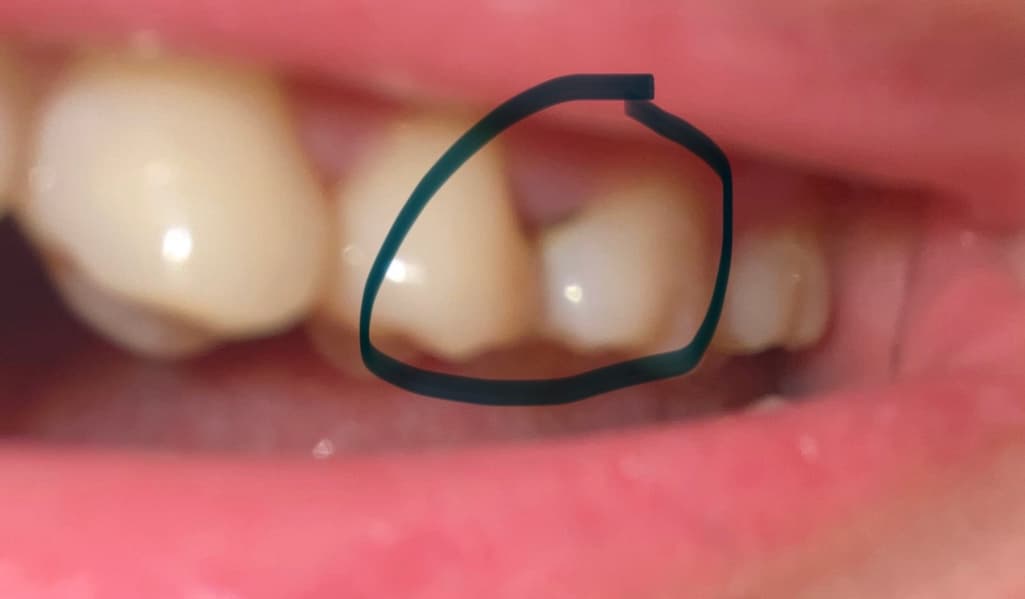

제가 치아에 충치가 생긴거 같아 치과를 가봤는데 충치가 맞고 육안으로 안 보이는 쪽에도 충치가 있어 인레이 치료를 해야할거 같다고 하셨는데 정말일까요? 일단 원래 가던 치과가 아니라 그냥 검진만 하러 간거라서 검진만 하고 나왔어요. 제가 좀 찾아보니까 레진으로도 가능하다고 하는데 인레이가 더 좋을까요? 레진은 좀 힘들까요? 그리고 인레이로 하면 치아 삭제를 얼마나 해야할까요? 교합면은 멀쩡한데 인레이 치료로 불필요한 삭제는 하는 것은 아닐까요? 질문으로 정리하면

사진에 보이는 부분은 레진으로도 치료가 가능할것으로 생각됩니다. 인접면에 충치가 있다면 인레이 치료를 하는것이 좋습니다. 인레이치료를 해야 한다면 인접면에도 충치가 있었을 가능성가능성이 있습니다.

육안상으로 보면 옆면에충치가 잇고 뿌리쪽에 충치가 잇는거 같습니다. 저 부위는 레진으로는 불가능하고 인레이나 크라운 치료를 하셔야될것같습니다.

옆면 충치는 레진으로 해두면 음식물이 잘 끼고, 깨지므로 인레이를 일반적으로 추천합니다